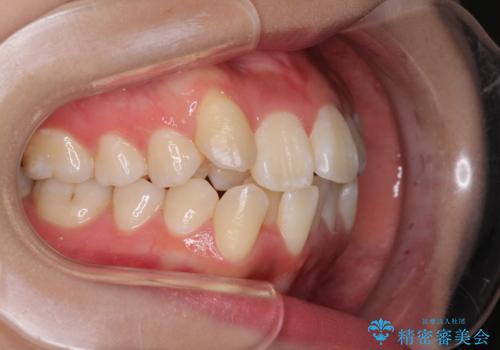

前歯の正中のズレを改善 目立たないワイヤー装置での抜歯矯正

移動量が多かったため、治療期間は通常より半年~1年ほど長くかかりましたが、上下の正中をほぼ同じ位置にまで移動させることができました。